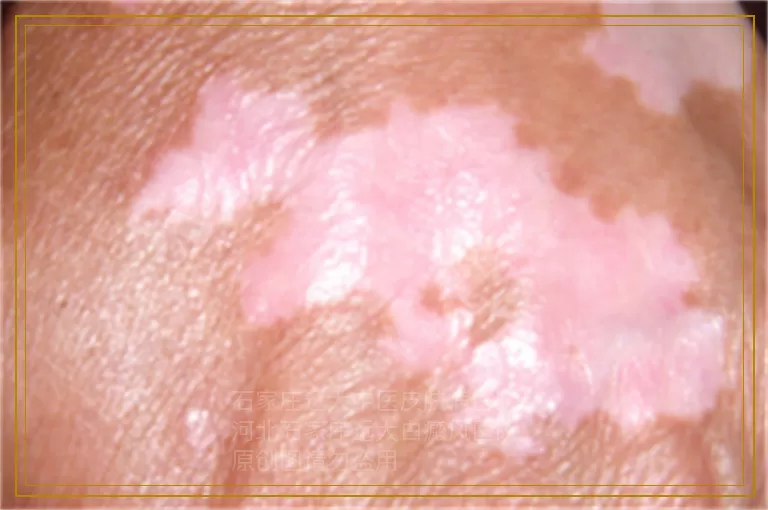

(您想免费联系在线专家?点我!)小知识:白癜风在我们的日常生活中是非常常见的一种皮肤病,该病的出现不仅会影响人们的美观还会给患者的健康带来严重的危害,在临床上许多患者在发生该病后还不清楚该病是么引起的,对于后期的护理、防止复发等是非常不利的。

相信对于白癜风这种顽固性疾病的治疗, 人们都有所了解吧,并不是一件十分容易的事情,但是如果治疗的不及时的话,就会给人们带来更大的危害,从而加大治疗的难度。那么白癜风能控制住吗?白癜风治疗的相关文章?